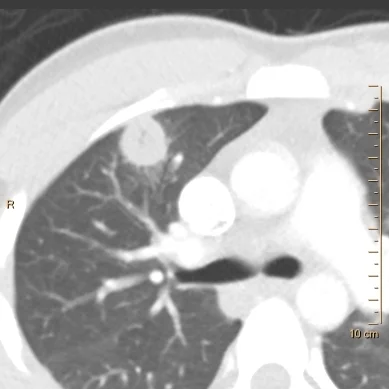

27 yo M, h/o IV drug use, presented with chest pain. CT with contrast performed according to the PE protocol shows a 2.2 cm nodule in the peripheral right upper lobe, with a subtle central cavitation.

Conventional CT shows right upper lobe nodule with subtle cavitation